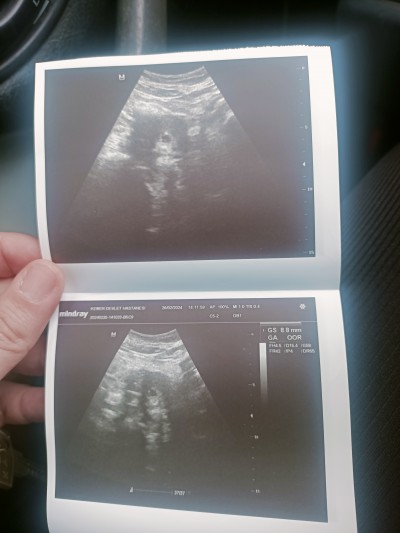

27.02 : 1750 kese ve bebeği gördük. Bs 8.8mm çıktı .Sanki HCG yavaş ilerliyor. Bir sıkıntı olabilirmi. Doktor sen 4haftalik gebesin dedi. Ama sistemde 6+4 gözüküyor nasıl oluyor

Normalde 6. Haftadayim ama utrosonda 4haftalik gibi dedi çapı da 8.8 mm dedi

Bende anlamadm 6+5 de yim bugün adetime göre. Doktor bana burda 4 gözüküyor dedi. Çapı da 8.8mm dedi. Bende hiçbisey anlamadım. Geç dollenmis dedi. Çok küçük dedi.

Kalp atışıni açtı bı ses duydum kapatti hemen valahi bende anlamadım dün 4 haftaliksin dedi bugün 5 haftaliksin ddi. Yok bebeği gördü içinde küçücuk bişey.  Doktorda kafayı yedi heralde. Biyerde bişey eksik de ben de anlamadim. Cuma günü gidicem tekrardan bakicak dün 8.8 mm di mesela bugün 9.4 mm olmuş